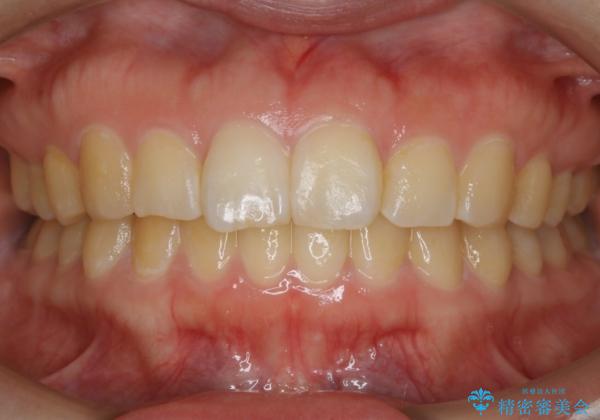

【非抜歯】ガタつきと歯軸を正して長持ちする歯へ

- 歯のガタつきと噛み合わせの改善を主訴に来院されました。

非抜歯で、少量の奥歯の移動と歯列の拡大・IPRを駆使して主訴を改善するための治療計画を立案しました。